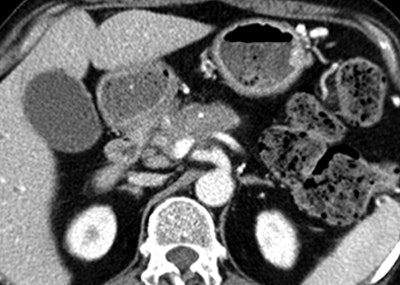

| Images obtained in a 63-year-old man with locally advanced pancreatic head cancer who was a member of the responder group. Above, transverse contrast-enhanced baseline CT image shows a locally advanced pancreatic head cancer mass. The long-axis diameter of the mass was 48.0 mm, and the perpendicular diameter was 22.2 mm. The bidimensional product was 1,016 mm2. At that time, the CA 19-9 level was 3,130 U/mL. |